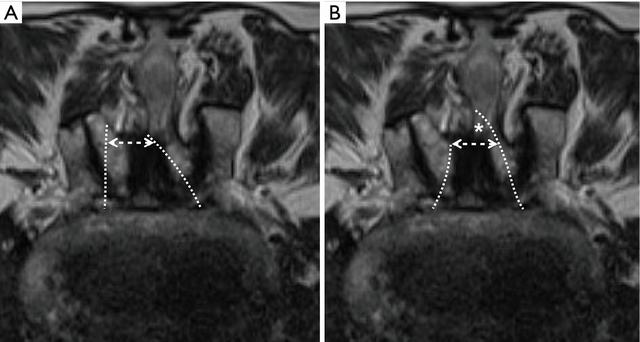

图4 对于严重椎管狭窄的患者,通过单侧入路(虚线)进行双侧减压可能会导致同侧小关节的过度破坏(A);从棘突根部去除更多的骨头(*)使对侧切开部分窗口(双箭头)从而尽可能的保留同侧小关节(B)。